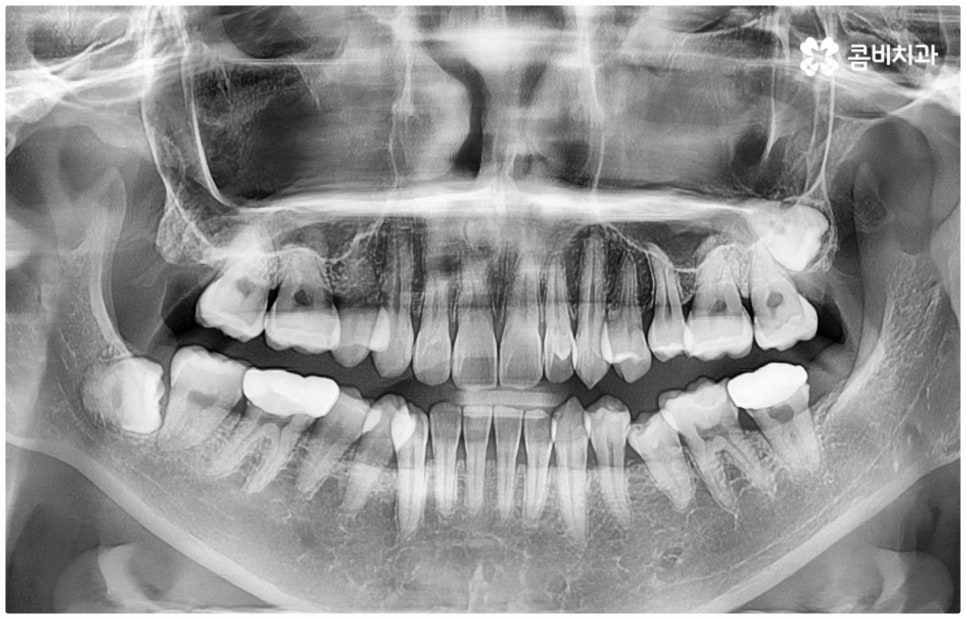

출처 아카이브 열기위아래 치열이 제대로 맞물리지 않으면 음식물을 씹을 때 어려움을 느끼거나 발음상 문제가 생길 수 있습니다. 이것을 부정교합이라고 하며, 그 종류는 상악과 하악의 골격적인 전후방 관계를 기준으로 1급, 2급, 3급으로 나눌 수 있어요. 위아래 어금니는 잘 맞물리는데 치열이 조금씩 삐뚤어져 있거나 치아 사이가 벌어져 있는 등 살짝씩 어긋난 부정교합은 1급, 위 어금니가 더 앞으로 나가있는 부정교합은 2급 (ex. 돌출입), 그리고 아래 어금니가 더 앞으로 나가있는 부정교합은 3급 (ex. 주걱턱) 으로 분류하게 되는데 이 중 오늘 살펴보려고 하는 것은 부정교합 3급에 해당하는 반대교합에 대한 거예요.

정상적인 교합은 윗 앞니가 아래 앞니를 살짝 덮는 정도로 윗니가 조금 더 앞으로 나와 있으면서 위아래 치아가 어금니까지 잘 맞물리는 것을 말하는데 반대교합은 위아래 앞니가 거꾸로 물리는 증상을 보이기 때문에 저작 활동 및 발음 조성이 원활하지 않게 되며 반대교합교정 등 적절한 치료를 받지 않고 방치할 경우 점점 더 주걱턱이 강화되는 쪽으로 뼈가 성장할 수 있어 될 수 있는 대로 빠른 시일 내에 원인을 분명하게 알아보고 그에 맞는 치료를 받는 것이 중요하다고 할 수 있어요.

반대교합의 원인은 크게 유전적인 원인과 후천적인 원인으로 나눌 수 있습니다. 골격적으로 상악보다 하악이 과성장하게 된 경우, 상악이 하악보다 열성장하게 된 경우를 골격성 반대교합이라고 하며 부모님께서 소위 말하는 주걱턱을 가지고 있다면 유전적으로 30% 정도 아이에게도 이러한 성향이 나타날 수 있으니 어릴 때부터 아이의 치열에 관심을 가지고 유치든 영구치든 상관없이 위아래 앞니가 거꾸로 물리는 현상이 나타나면 바로 치과로 가셔서 검진 및 반대교합교정 치료를 받아볼 수 있도록 도와주시길 권유드리고 있어요.

반대교합의 경우 보통 두 원인이 혼재되어 나타나는 경우가 많으며 또한 환자분들의 상황에 따라 정확한 치료가 달라지기 때문에 꼼꼼한 검진 후 각자에 맞는 반대교합교정 치료를 통해 이를 바로잡아 주시길 권유드리고 있어요. 검진과 치료를 받을 때는 3D CT와 같은 정밀 검사 기계를 갖추고 있는 치과에서 임상 경험이 풍부하고 뛰어난 노하우와 기술을 가지고 있는 숙련된 의료진에게 반대교합교정 치료를 진행하는 것이 좋을 거예요.